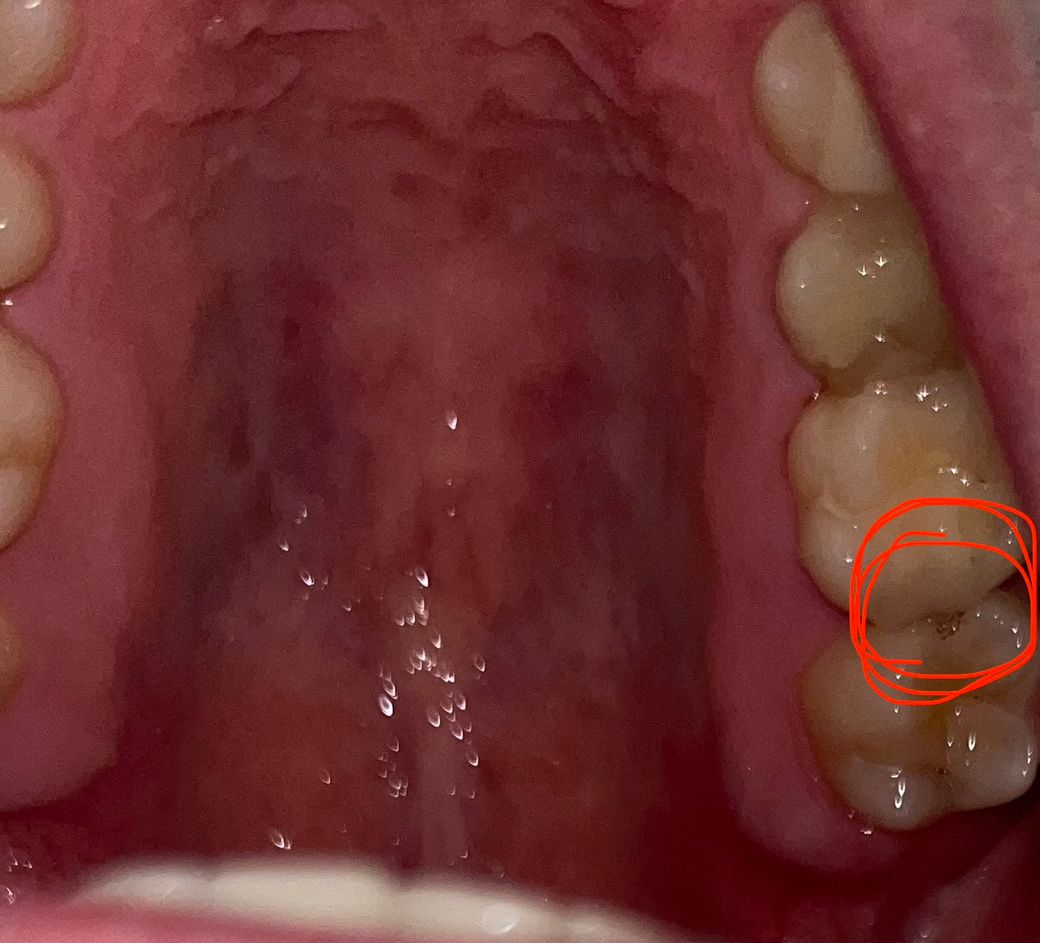

어금니에 구멍이난거같아요 음식물이 자주 낍니다

2달정도 됐는데 평소에 안아프고 밥먹을때 음식물이 자주 끼고요 혀로 느껴봤을때 살짝 뚫려있는 느낌이 들어요 충치인가요..?ㅠㅠ 심각한걸까요?

사진으로 보이는 이것은 인접면에 충치가 생긴 것으로 보입니다. 충치가 생기게 되고 빈 공간이 생기게 되어 해당 부위에 이물질이 계속 들어가게 됨으로써 충치가 더 진행된 것으로 보입니다. 우선 충치를 제거해야 하며 충치를 제거했을 경우 신경까지 충치가 진행되어 있다면 신경 치료가 필요할 수 있습니다.

자세한 확인을 위해서 치과에서 진료를 받아보는 것을 권유드립니다.

치아 사이에 충치가 생겨서 구멍이 생긴거 같습니다. 치과에 가셔서 엑스레이를 찍어보시고 치료를 받으시는게 좋을것같습니다.

네 인접면 충치가 맞습니다 음식물이 자주끼어있으면 충치가 더 진행될 겁니다 신경치료 가능성이 있고 일단 인레이를 시도해봅니다